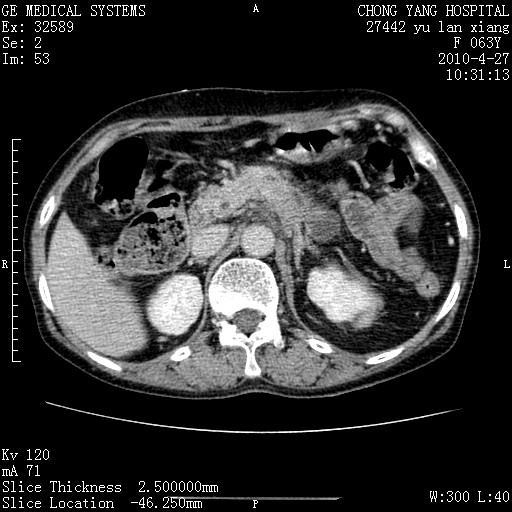

标题: CT26066:F63Y 上腹正中压痛半月,CA199:7400u/ml,MR示胰腺炎伴 [打印本页]

胰腺癌侵犯腹腔动脉干-分支、胃壁、左侧膈肌伴胰周及腹膜后淋巴结转移、胆囊切除术后。

胰腺癌侵犯腹腔动脉干-分支、胃壁、左侧膈肌伴胰周及腹膜后淋巴结转移、胆囊未显影。